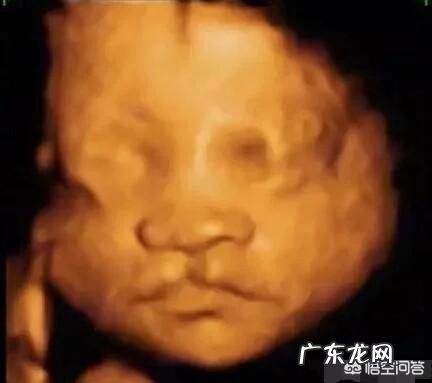

腹中胎儿唇腭裂是怎样引起的?

唇腭裂又名“兔唇”,是一种多基因遗传病 。但是至今发病原因尚不明确,可能是遗传因素、环境因素、孕后用药病理因素或者孕期叶酸缺乏等有关 。

胎儿唇腭裂,也叫兔唇,是一种先天性的发育畸形 。主要是由遗传因素、外界环境因素、母体因素引起 。